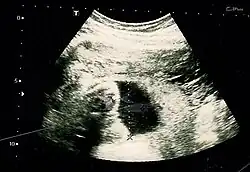

A 23 week abdominal pregnancy on ultrasound showing a normal fetus and amniotic fluid

Image by Dahab AA, Aburass R, Shawkat W, Babgi R, Essa O, Mujallid RH

Suspicion of an abdominal pregnancy is raised when the baby‘s parts can be easily felt, or the lie is abnormal, the cervix is displaced, or there is failed induction of labor.[4] X-rays can be used to aid diagnosis.[9]